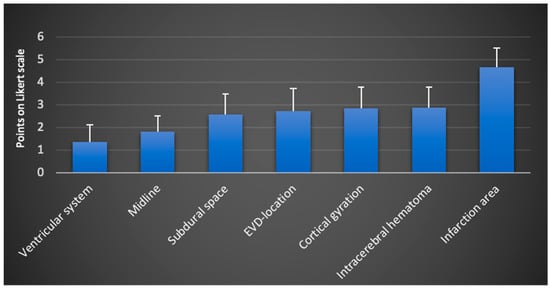

In most cases, multiple anatomical and pathological image markers could be assessed from a single image. In some instances, a focused examination was conducted when addressing a specific clinical question. For the qualitative evaluation, all available images and videos from the examinations were utilized. The overall results of the evaluation are presented in Figure 2.

Figure 2.

Total scores including all examiners (mean values and standard deviation on the Likert scale from 1: very good visualization to 5: insufficient visualization and 6 points: structure not found; N = 6 examiners; n = 158 TUS sessions).

Overall, the image markers ventricular system, ML, and subdural space received the best (lowest) scores. Regarding the EVD location, all examiners noted a negative impact from a tract hemorrhage, which occurred in two cases (see Figure 1f). ICHs were correctly identified by all examiners, although the presence of a resorption edema or infarct in close proximity negatively affected assessability. By a large margin, the visualization of infarction areas received the lowest ratings from all examiners.